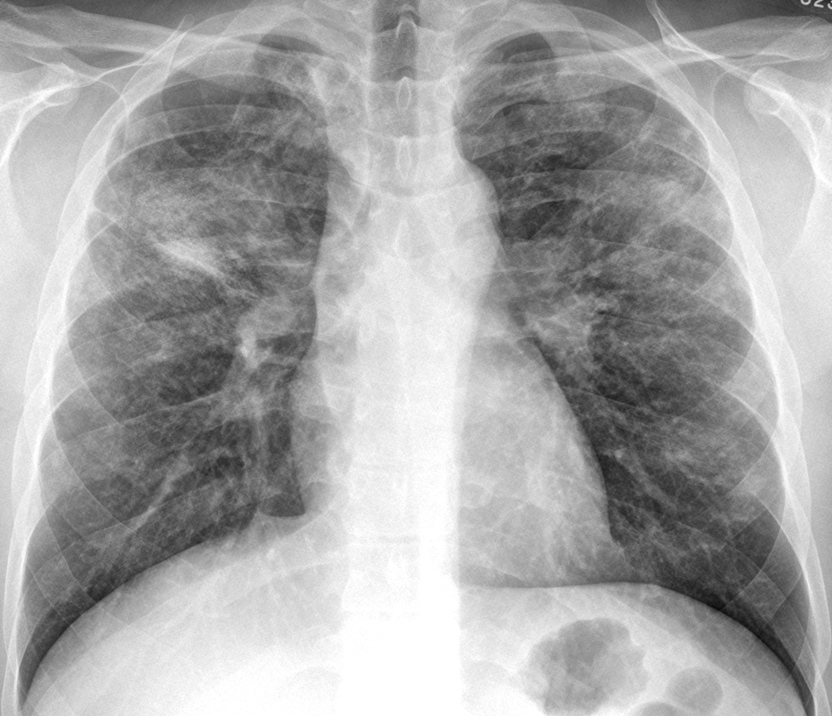

Sarcoid

Sarcoid Late Case 8

Sarcoid Late

Case 8